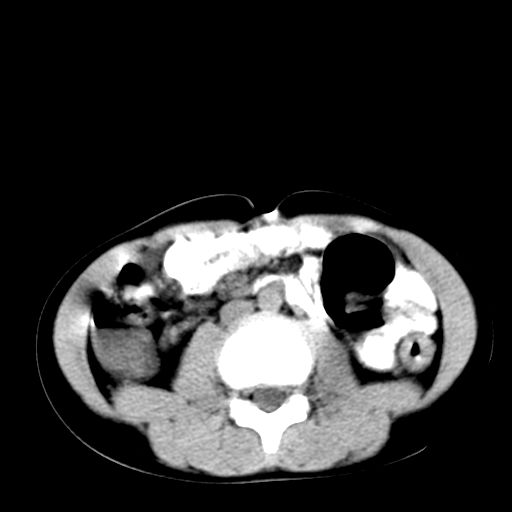

腹部好象未见异常。

腹部ct平扫未见明确异常

腹部ct平扫不能提示哪里有病变。